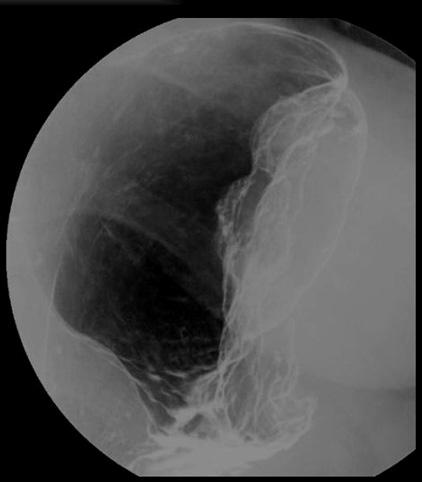

Criteria of Hist.ClassificationMalignant Lymphoma/Malignant lymphoma

LocationStomach/More than one of above

Technique, MethodX-ray

Size40 -

Depth of Tumor Invasionserosa (adventitia)